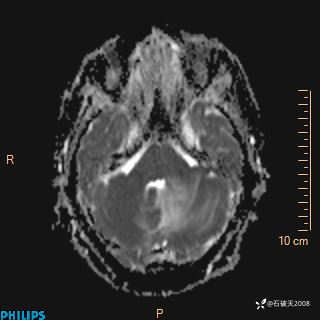

ADC